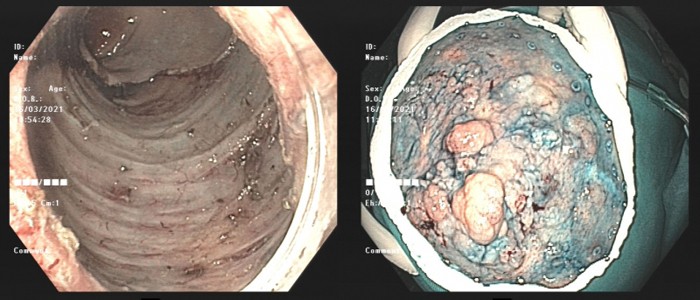

Hình ảnh nội soi đường tiêu hóa phát hiện đám tổn thương dạng u ống tuyến lan tỏa tại trực tràng. Tổn thương chiếm 2/3 chu vi trực tràng lan xuống ống hậu môn.

Kết quả giải phẫu mẫu bệnh phẩm cho thấy, bệnh nhân bị tổn thương tiền ung thư trực tràng. Sau hội chẩn, các bác sĩ chỉ định nội soi can thiệp cắt hớt niêm mạc để loại bỏ các khối polyp lớn trong lòng trực tràng.